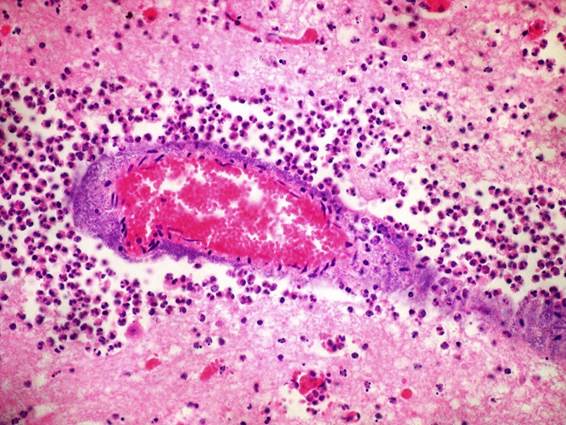

A la histopatología, las lesiones se caracterizaban por severa leptomeningitis, coroiditis, y periventriculitis fibrino-supurativa, con vasculitis leucocitoclástica, trombosis con numerosas colonias bacterianas cocoides Gram-negativas, y manguitos perivasculares de neutrófilos y macrófagos de 1-3 células de espesor.

Además de las lesiones nerviosas, en los casos Nº 1 y 2 había peritonitis fibrino-supurativa y los riñones tenían focos amarillentos de 1 mm en la corteza. A la histología, las lesiones renales se caracterizaban por pielonefritis neutrofílica e histiocítica, multifocal, ascendente desde la pelvis renal a la unión cortico-medular. En el caso Nº 4 había también lesiones de pericarditis fibrino-supurativa (corazón en "pan y mantequilla"), similar a la retículo-pericarditis traumática, que se descartó por la ausencia de reticulitis y cuerpos extraños. Microscópicamente había miocarditis supurativa localizada en los músculos papilares ventriculares, severa, con focos de necrosis, multifocales-coalescentes, bacterias intralesionales, y vasculitis leucitoclástica con trombos en los pequeños vasos. La coloración de PAS y GMS descartó la vasculitis micótica en todos los casos.

Los bloques de parafina remitidos (Casos Nº 1 y 2) resultaron inmunoperoxidasa positivos para H. somni, con marcación de las colonias bacterianas dentro de las lesiones cerebrales, cardíacas y renales.

Las lesiones histológicas de vasculitis y trombosis, con colonias bacterianas, encontradas en todos los casos son altamente sugestivas de infección por H. somni (Cantile y Youssef, 2016). La coloración con PAS y GMS permitió ver las lesiones de vasculitis y descartar la presencia de hifas causantes de vasculitis. Otros agentes piógenos (Trueperella pyogenes, Listeria monocytogenes, Escherichia coli, Streptococcus spp., etc.) que pueden causar miocarditis supurativa o necrotizante fueron descartados por la distribución de las lesiones y porque no afectan los músculos papilares (O’Toole y Sondgeroth, 2016). También se descartó la miocarditis por Clostridium chauvoei (blackleg) que produce lesiones macroscópicas características e infiltrado inflamatorio sero-hemorrágico y en ocasiones con presencia de bacilos clostridiales (Dutra et al., 2015).